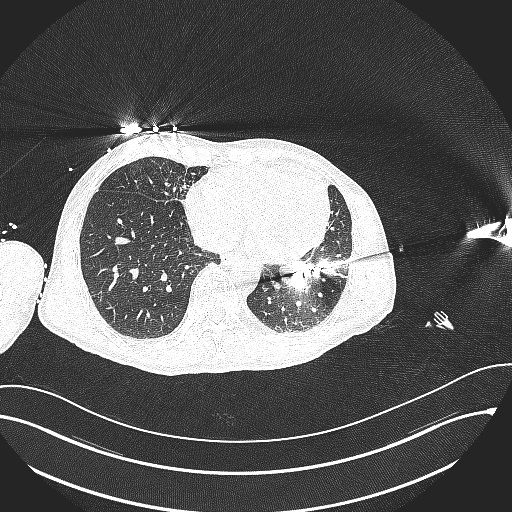

心胸外科实施的微波消融术是在CT引导下,将一根直径仅2mm的微波针穿刺到肿瘤部位,使肿瘤局部温度瞬间升高到80-100℃,实现“烧死”肿瘤的目标。该术式创伤小、安全性高、疗效好,可以提高患者的生活质量,并延长生存时间,是目前应用前景较好的治疗方式之一。术后4至6周复查胸部增强CT,并以此为基线进行评价,术后2年内每3个月复查胸部CT,2年后每6个月复查一次。

术前与术中对比图